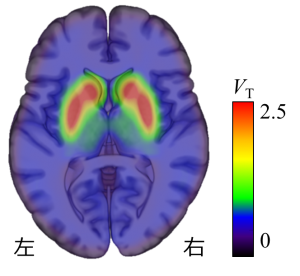

次に、同一被験者に、脳内のドーパミンD2受容体に結合する[11C]ラクロプライドという薬剤を用いてPET検査を行い、脳内の線条体と呼ばれる部位のドーパミンD2受容体の密度を計測しました(図3)。

図3 線条体におけるドーパミンD2受容体のPET画像

脳内のドーパミンD2受容体を検討できる[11C]ラクロプライドという薬剤を用いてPET検査を行い、モデル解析により脳内の線条体と呼ばれる部位のドーパミンD2受容体の密度を測定した。赤いほどドーパミン受容体の密度が高いことを示している。